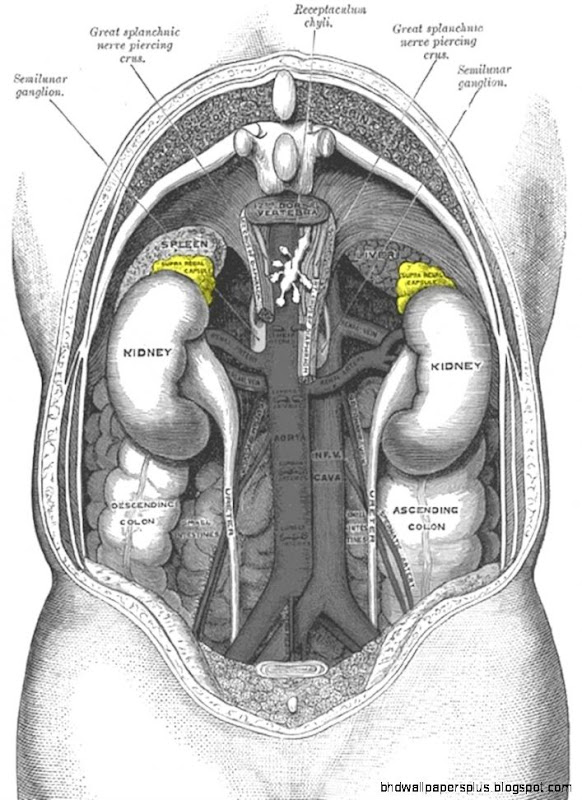

Adrenal glands Grays anatomy illustration Radiology Case

Filename : adrenal-glands-grays-anatomy-illustration-radiology-case.jpg